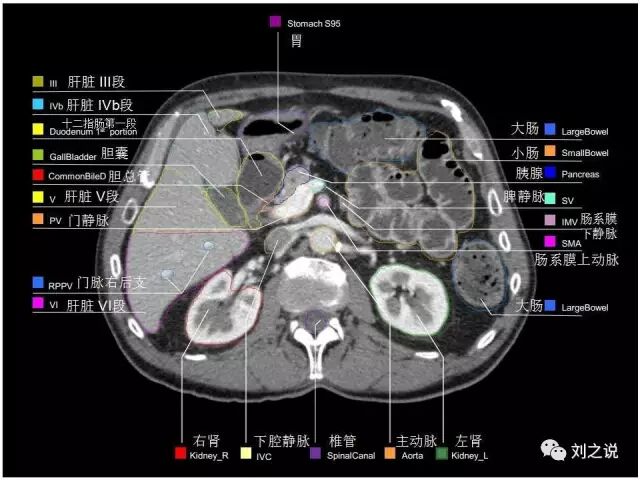

参考RTOG共识和3D-body解剖。

来源:刘之说